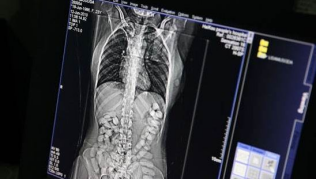

不忍直视!男子排出123粒毒丸……

缴获可卡因毒丸123粒

净重1580.44克

这是北京海关近5年来

在旅检渠道查获的

最大一宗人体藏毒走私案

在现场调查过程中

该犯罪嫌疑人从体内排出

4粒被乳白色塑料膜和橡胶膜

包裹的柱形物

初检为可卡因

海关关员将其移交缉私部门后

该犯罪嫌疑人

被送往指定医疗机构

做进一步检查和监护排毒

随后又多次排出了

藏在体内的毒丸

经专业机构检测

为高纯度可卡因